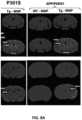

FIG.8A shows pre- and post-contrast MRI images for T1-weighted spin echo (Tlw-SE) and fast spin echo inversion recovery (FSE-IR), demonstrating signal enhancement in delayed post-contrast scans of Tg P301S mice and APP/PSEN1 mice treated with WNP relative to age-matched WT controls.

FIG.8B shows box and whisker plots demonstrating signal enhancement in Tg P301S mice and APP/PSEN1 mice treated with WNP relative to WT counterparts and UC-treated Tg animals for both Tlw-SE and FSE-IR sequences. The dotted line indicates the signal threshold for determining sensitivity (two standard deviations above baseline noise, ˜6%).

FIG.8C shows ROC curves plotting true positive TPF against FPF, demonstrating WNP accuracy in identifying early age Tg animals. A fitted curve connects the observed operating points. AUC is calculated using the fitted curve, and sensitivity (true positive rate) and specificity (true negative rate) are listed.

Two month old P301S mice and APP/PSEN1 were injected with WNP and imaged using the same T1-weighted sequences as used with the ADx-002 nanoparticles. No signal enhancement was observed in the WT mice models, whereas the Tg mice (P301S and APP/PSEN1) showed distinct signal enhancement in the cortex and hippocampus regions and were identified as positives (FIGS.8A and8B). Group statistical analysis (FIGS.8B and8C) revealed that the VIM-targeted WNP contrast agents showed overall AUC and accuracy of ˜1.00. The phosphorylation status of tau in transgenic mice was confirmed by immunofluorescence (FIG.9).